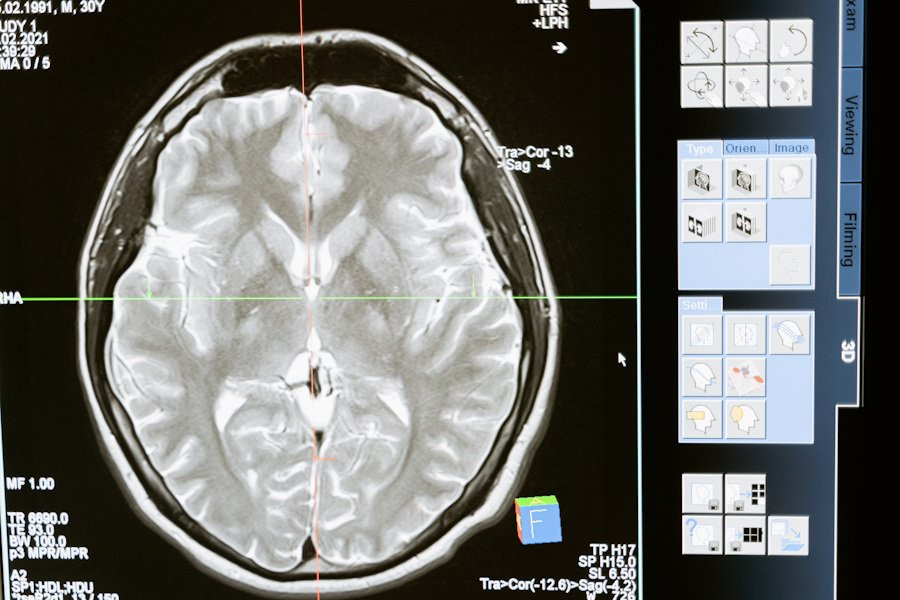

Российские ученые разработали уникальную платформу для борьбы с одной из самых опасных опухолей мозга — глиомой. Этот проект, направленный на улучшение диагностики и лечения, разрабатывается под руководством профессора Галины Павловой в НМИЦ нейрохирургии имени академика Н.Н. Бурденко Минздрава РФ.

Согласно изданию "Известия", платформа включает четыре ключевых направления: улучшение методов лечения, создание новых радиофармпрепаратов для диагностики, разработку препаратов для повышения эффективности лучевой терапии и применение таргетной терапии, которая позволяет доставлять лекарство напрямую в опухоль.

Главной особенностью этой платформы является использование аптамеров — молекул, которые способны распознавать опухолевые клетки и не затрагивать здоровые ткани, что значительно уменьшает побочные эффекты. Внедрение этих технологий в клиническую практику может стать революционным шагом в лечении глиомы и других видов рака мозга.

Доклинические испытания планируются уже к 2025 году, что дает надежду на значительное улучшение прогнозов для пациентов, особенно с высокоагрессивными формами опухолей.